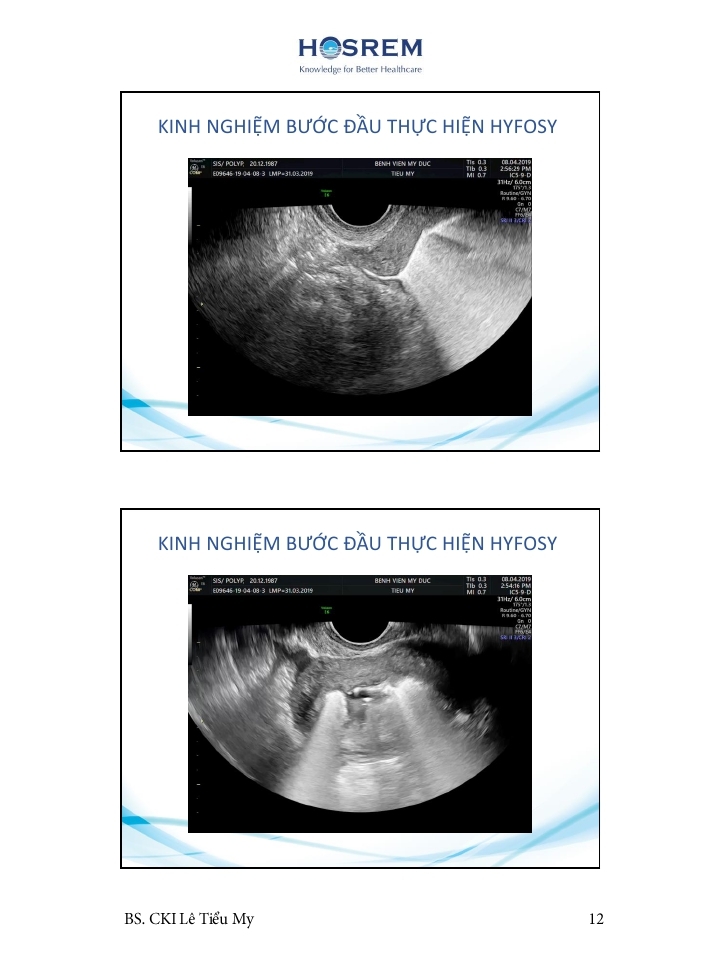

Các phương pháp đánh giá ống dẫn trứng